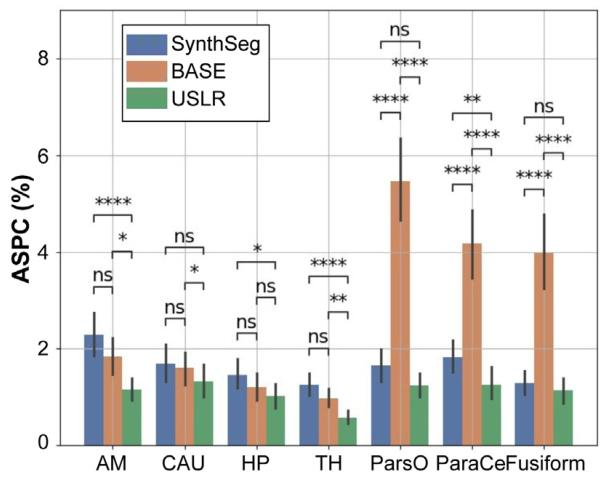

Fig. 8. Absolute symmetrised percent change (ASPC) for different cortical and subcortical brain regions: amygdala (AM); caudate (CAU); hippocampus (HP); thalamus(TH); pars opercularis (ParsO); paracentral (ParaCe); and fusiform. Three segmentationmethods are compared: (i) SynthSeg, which is the original cross-sectional segmentations; (ii) BASE, which is the longitudinal refinement using one acquisition as referencetemplate; and (iii) USLR. A Wilcoxon-rank test is used for statistical significance with(*) 1 ⋅ 10−2 < 𝑝 < 5 ⋅ 10−2 , () 1 ⋅ 10−3 < 𝑝 < 1 ⋅ 10−2 , (*) 1 ⋅ 10−4 < 𝑝 < 1 ⋅ 10−3 and() 𝑝 < 1 ⋅ 10−4 thresholds.

图8 不同皮质及皮质下脑区的绝对对称化百分比变化(ASPC):杏仁核(AM)、尾状核(CAU)、海马(HP)、丘脑(TH)、岛盖部(ParsO)、中央旁小叶(ParaCe)和梭状回。比较了三种分割方法:(i)SynthSeg,即原始横断面分割;(ii)BASE,即使用一次采集作为参考模板的纵向优化;(iii)USLR。采用Wilcoxon秩检验进行统计显著性分析,显著性水平标注如下:()1×10⁻²<𝑝<5×10⁻²,(**)1×10⁻³<𝑝<1×10⁻²,(**)1×10⁻⁴<𝑝<1×10⁻³,()𝑝<1×10⁻⁴。